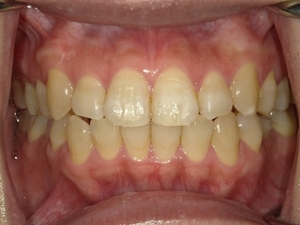

◯ご相談内容:歯並びが気になる◯矯正の種類:マウスピース型矯正「インビザラインGO」◯治療期間:20週間◯治療費用:44万円(税込)